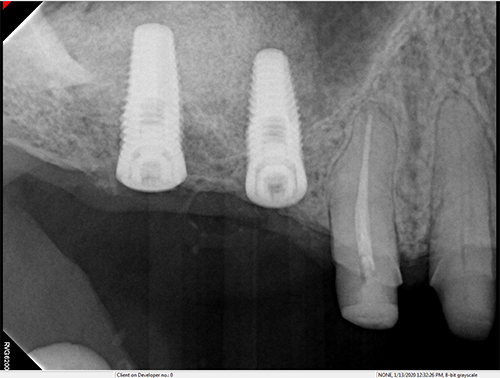

Bilateral Sinus Augmentation and 6 Maxillary Implants